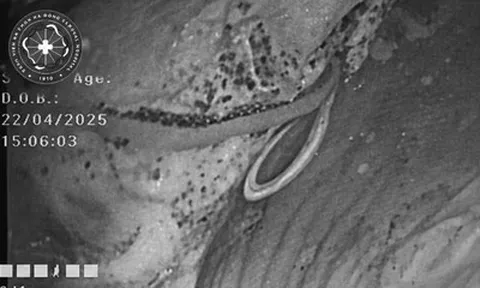

Và mới đây, một trường hợp tương tự tiếp tục được ghi nhận, gióng lên hồi chuông cảnh báo. Như đã đề cập, bệnh nhi đến khám tại Vũ Hán với biểu hiện nhìn mờ kéo dài. Kết quả kiểm tra cho thấy cả hai mắt đều nhiễm ấu trùng giun tròn Toxocariasis, gây tổn thương nghiêm trọng đến thị lực.

Qua thăm khám chuyên sâu, bác sĩ chẩn đoán bệnh nhi bị thoái hóa điểm vàng ở mắt phải và bệnh võng mạc trung tâm thanh dịch ở cả hai mắt. Đáng chú ý, cả hai mắt đều phát hiện nhiễm ấu trùng giun tròn Toxocariasis.

Sau khi xâm nhập qua đường tiêu hóa, trứng giun nở thành ấu trùng, xuyên qua thành ruột và theo đường máu di chuyển khắp cơ thể. Trong một số trường hợp, chúng có thể xâm nhập vào nhãn cầu, gây phản ứng viêm và tổn thương mô nghiêm trọng.

Khi ấu trùng xâm nhập sâu vào võng mạc, chúng có thể gây ra hàng loạt biến chứng như viêm nội nhãn, tổn thương võng mạc hoặc đục thủy tinh thể. Trường hợp nặng có thể dẫn đến teo nhãn cầu, thậm chí mù lòa.